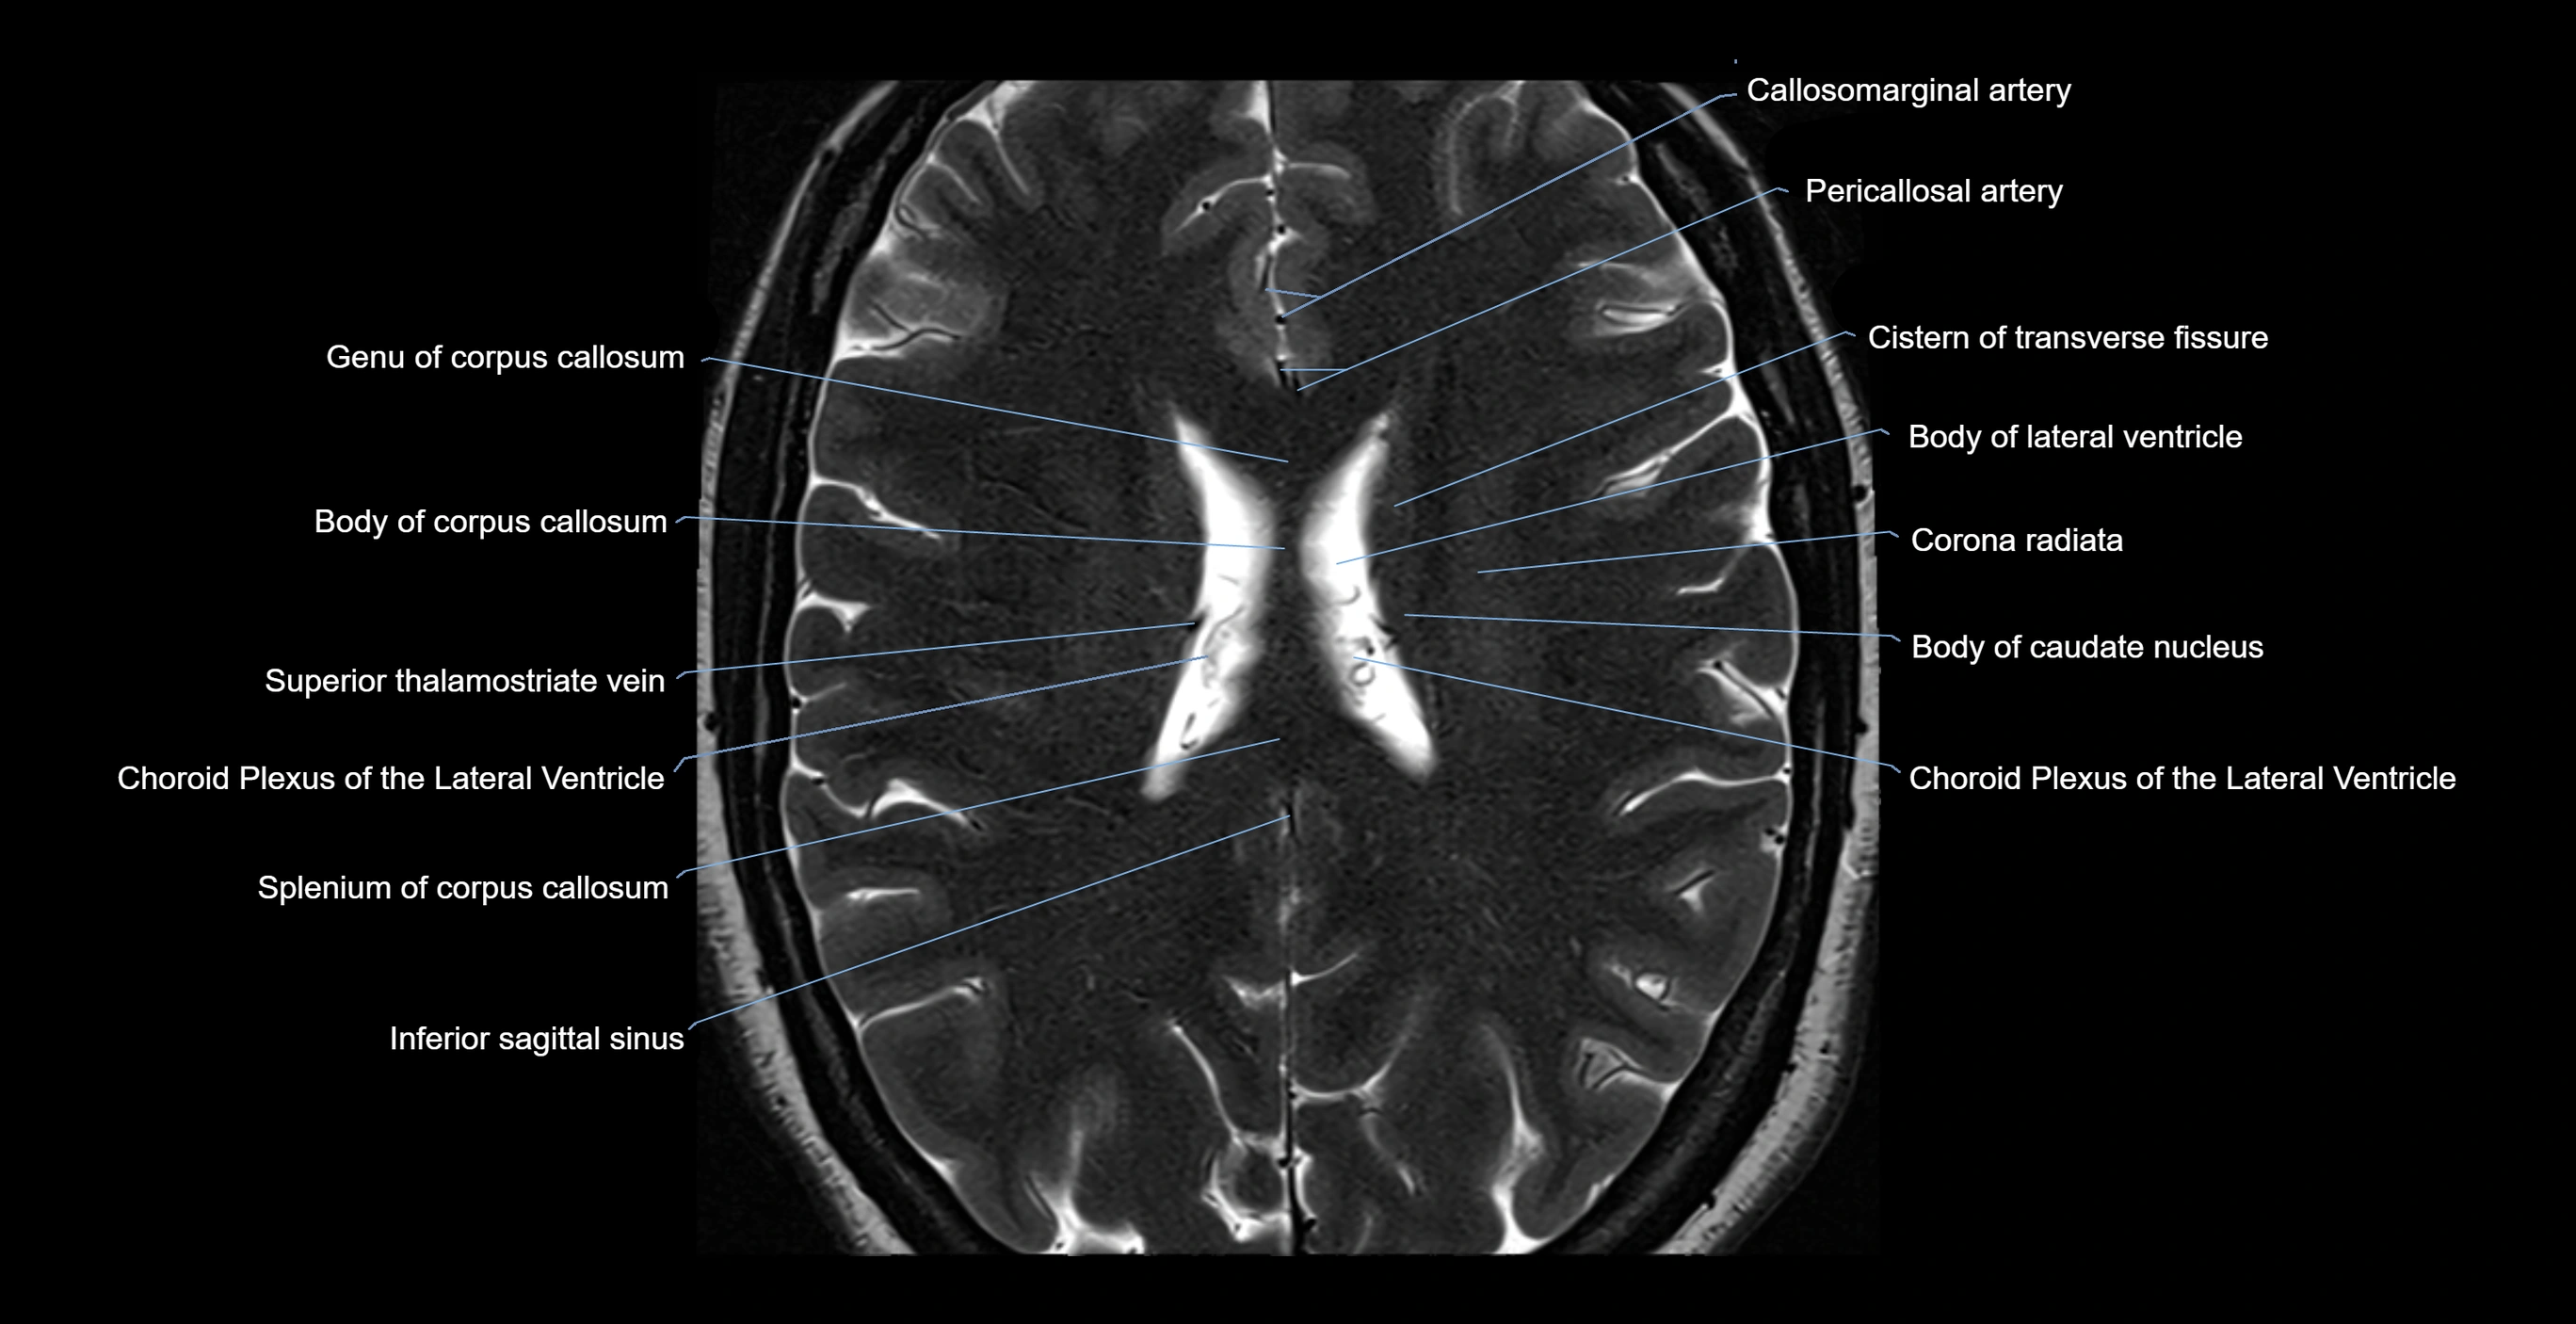

- Body of corpus callosum

- Body of lateral ventricle

- Callosomarginal artery

- Choroid plexus of the lateral ventricle

- Cistern of transverse fissure

- Corona radiata

- Inferior sagittal sinus

- Splenium of corpus callosum

- Superior thalamostriate vein